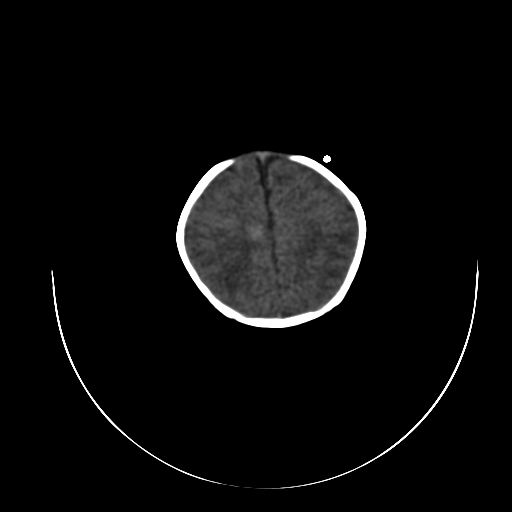

标题: PED0840:女,1.6岁,全身粘膜黄染6天,医生考虑新生儿胆红素 [打印本页]

标题: PED0840:女,1.6岁,全身粘膜黄染6天,医生考虑新生儿胆红素

正常  机器伪影

双侧脑实质多发低密度灶;是图象燥声?烟雾病?         右基底节到顶叶高密度灶,长轴大于宽度,伪影?出血灶??

机器伪影,每层都有,如果是病灶那不成了园柱形的了吗

每层都有且没有改变,应该是机器伪影。

谢谢拉,经过第二次扫描,就没有看见了,

开始我们也怀疑是机器伪影,但又怕是其他的。

不敢下结论。